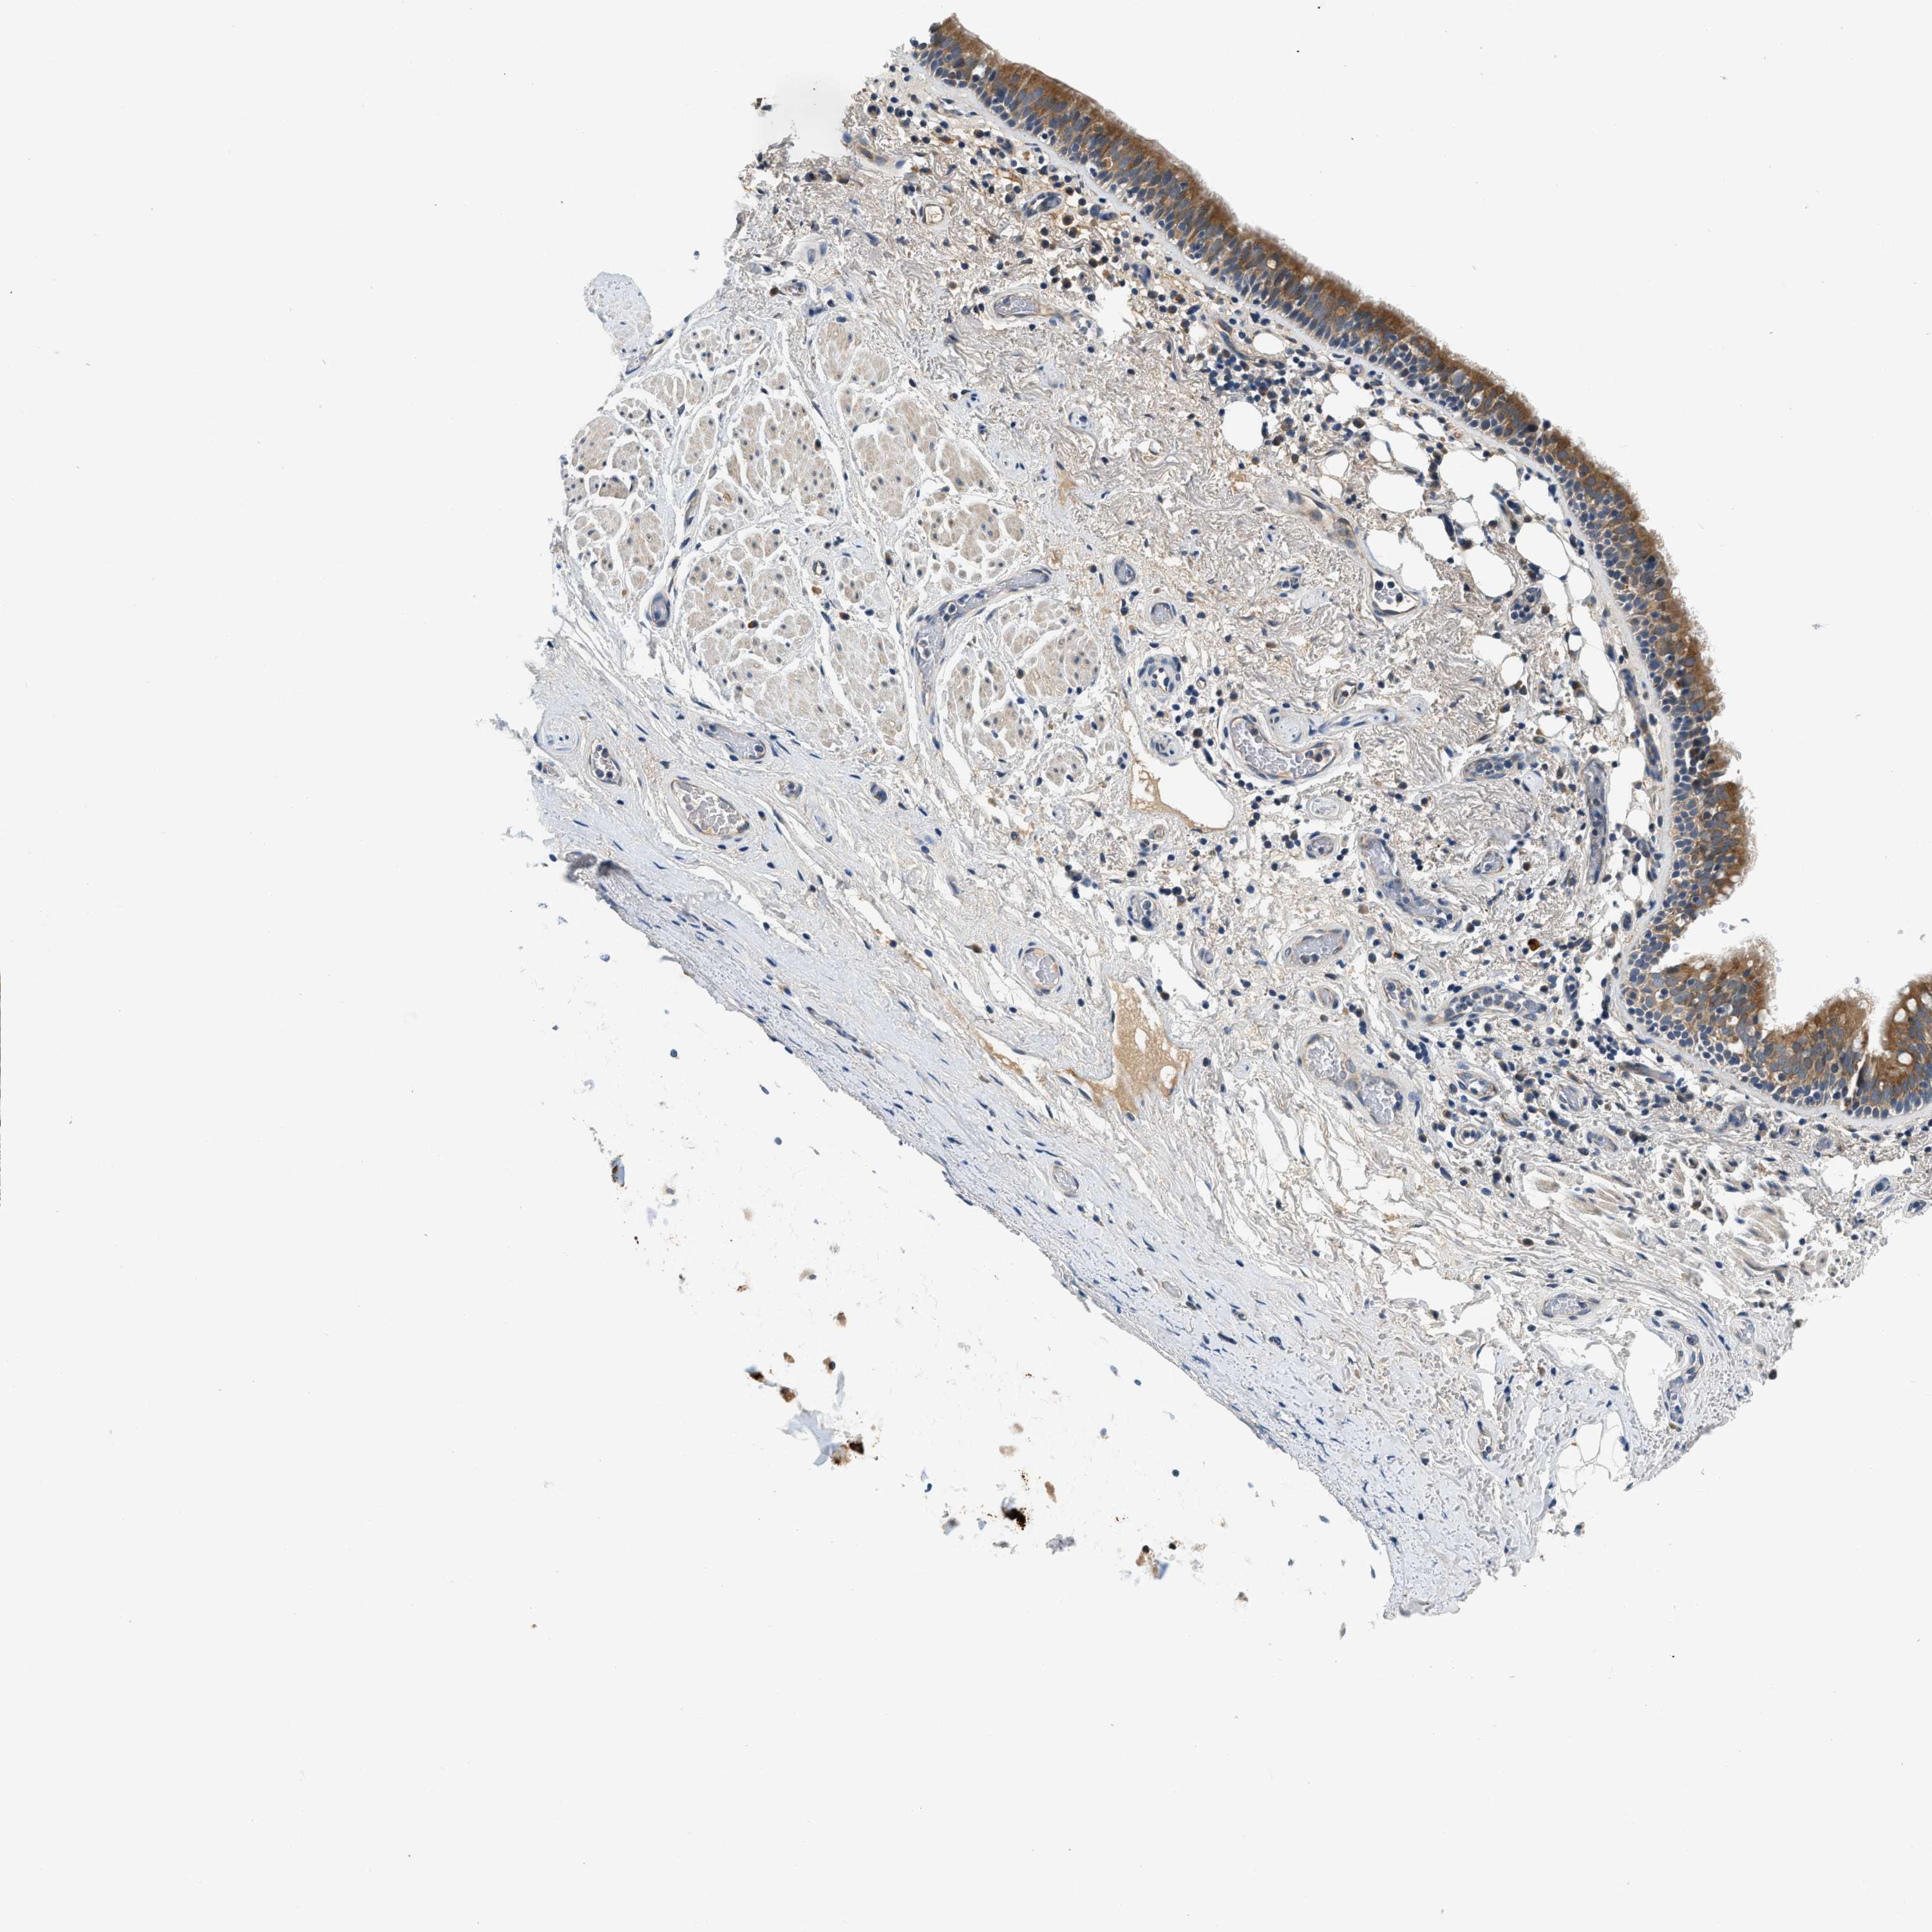

BRONCHUS - Antibody stainingi

Antibody staining in the annotated cell types in the current human tissue is reported as not detected, low, medium, or high, based on conventional immunohistochemistry profiling in selected tissues. This score is based on the combination of the staining intensity and fraction of stained cells.

Each image is clickable and will lead to virtual microscopy that enables deeper exploration of all samples and also displays staining intensity scores, fraction scores and subcellular localization as well as patient and tissue information for each sample.

Antibody HPA019226Antibody HPA031249

Respiratory epithelial cells MediumHigh